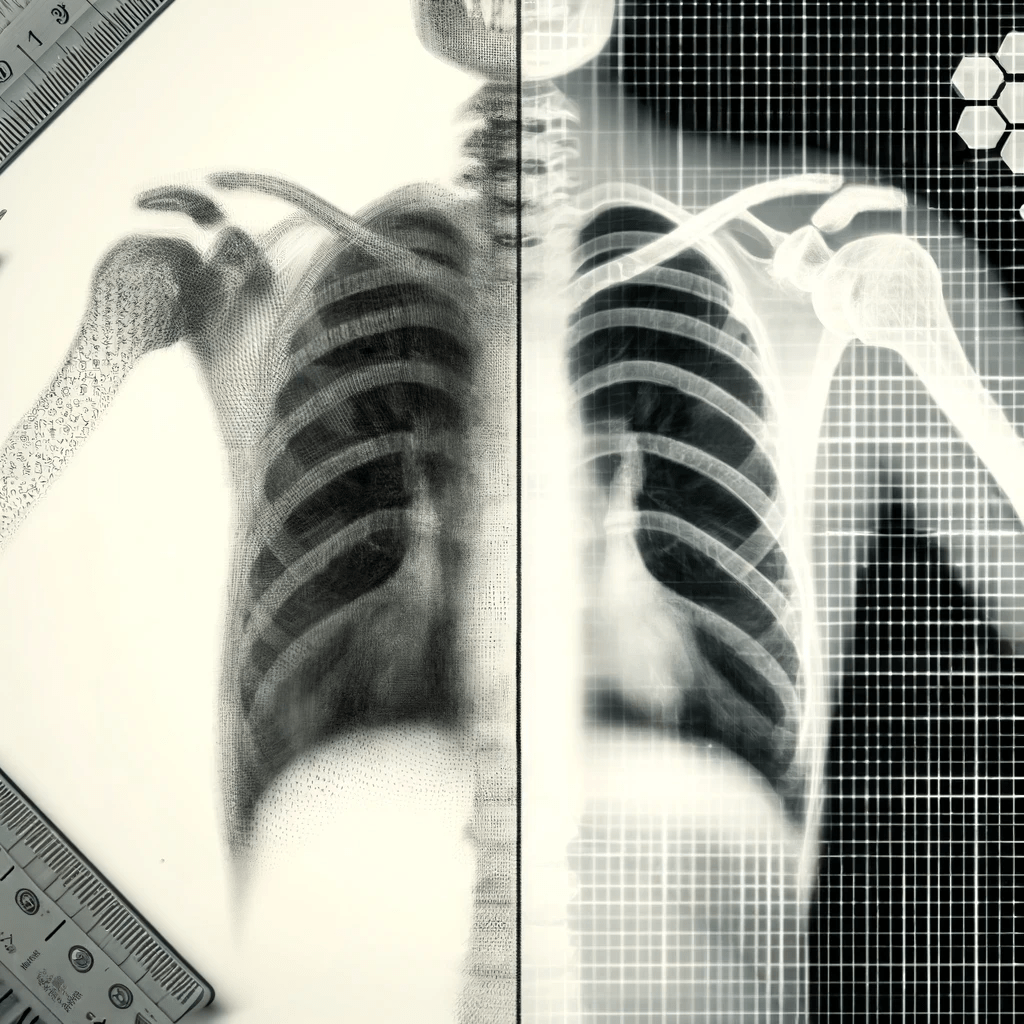

Inverse Problems in Radiology